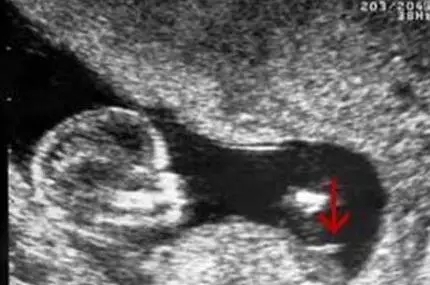

三、国外新奇小肿块原理

个别有经验的妈妈还有另一种看图方式:十一至十三周,所有的胎儿都会在双腿之间长出一个小肿块,而这个肿块的角度则会显示出它是个男孩还是女孩。据说如果小肿块翘起来30度以上就是男孩,但如果小角度就是女孩。请看下面的例子。

2017生男生女计算器

小肿块没有指向三十度以上 - 事实上它几乎是水平的!

小肿块以一个陡峭的角度向上指,显示这个胎儿是个男孩。

如果你可以得到一张侧面图,那么它应该会给你提供一个很好的观察小肿块的角度。